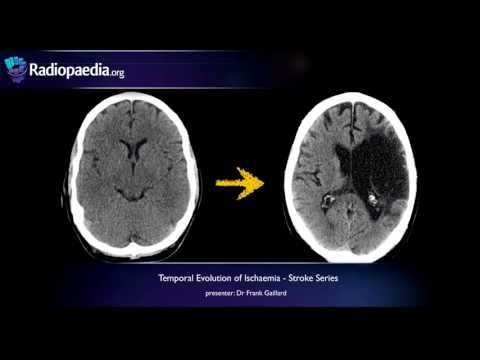

КТ головного мозга: нормальные изображения и изображения при геморрагическом инсульте | Признаки «вихрь», «черная дыра», «смешение», «пятно» и «островок» *Случаи Гиперденсивная зона — 0:00 Признак «вихрь» — 1:31 Признак «черная дыра» — 5:38 Признак «смешивания» — 7:04 Признак «сателлит» — 8:13 Признак «пятно» — 9:23 Признак «островка» — 10:55 — Гиперденсивная зона: наиболее характерным признаком острого геморрагического инсульта на КТ без контрастирования является гиперденсивная (яркая) зона в паренхиме головного мозга. Это обусловлено высоким ослаблением крови в острой фазе по сравнению с мозговой тканью. — Окружающий отек: по мере развития кровоизлияния может развиваться окружающий отек низкой плотности, который обычно становится более выраженным через несколько дней после начала. Этот отек может дополнительно способствовать развитию масс-эффекта. Симптом «вихря»: характеризуется участками смешанной плотности в области кровоизлияния. Он представляет собой сочетание гиперденсных (ярких) и гиподенсных (темных) участков внутри кровоизлияния, создавая видимость завихрений крови на разных стадиях свертывания. Симптом «вихря» часто ассоциируется с большим объемом кровоизлияния, потенциальным расширением кровоизлияния и повышением внутричерепного давления вследствие эффекта массы скопившейся крови. У пациентов с этим признаком на первичной КТ может быть более высокий риск ухудшения состояния и неблагоприятных исходов по сравнению с пациентами без этого признака. Эффект массы: деформация, сдавление или облитерация желудочков и борозд головного мозга вблизи места кровоизлияния. Этот эффект обусловлен накоплением большого объема крови в паренхиме мозга, что приводит к повышению внутричерепного давления и сдавливанию прилегающих тканей мозга. Симптом «черной дыры»: Относительно гиподенсная (более темная) область внутри гиперденсного (яркого) геморрагического очага, часто круглой или овальной формы. Эта темная область окружена более яркими участками острого кровоизлияния, напоминающими «черную дыру». Разница между симптомом «черной дыры» и кровоизлиянием должна составлять не менее 28 единиц Хаунсфилда. Симптом «смешанного»: Гематома смешанной плотности, состоящая из гиперденсной области, прилегающей к гиподенсной. Четкая граница/сопряжение между гиперденсной и гиподенсной областями. Разница между этими двумя областями должна составлять не менее 18 единиц Хаунсфилда. Симптом «сателлита»: Небольшая гиперденсная область, отделенная от основной гематомы. Диаметр области должен быть менее 10 мм. Расстояние между основной гематомой и сателлитным признаком не должно превышать 20 мм. Не должна располагаться в субарахноидальном пространстве или желудочках. Признак пятна: один или несколько участков контрастного усиления в области острого внутримозгового кровоизлияния при КТ-сканировании. Эти пятна визуализируются во время артериальной фазы введения контраста, указывая на активное кровотечение внутри гематомы. – Ослабление более чем в два раза превышает интенсивность кровоизлияния. – Рентгеноплотность = 120 HU. Признак острова: 3 или более небольших гематомы, отделенных от первичной.